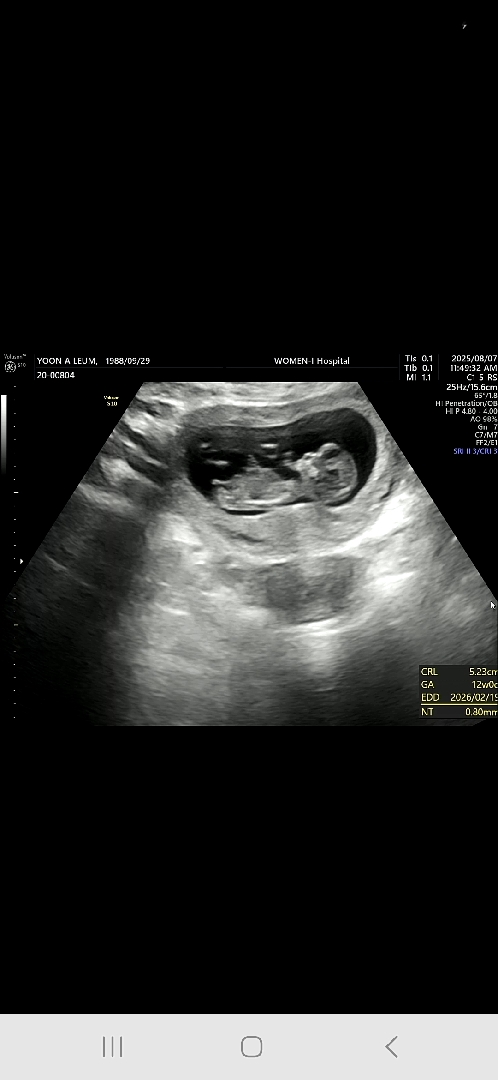

아들요~

2026년 2월 베동

각도법 좀 봐주세요ㅠㅠ

성별 좀 봐주세요~~~~!!!!!!!